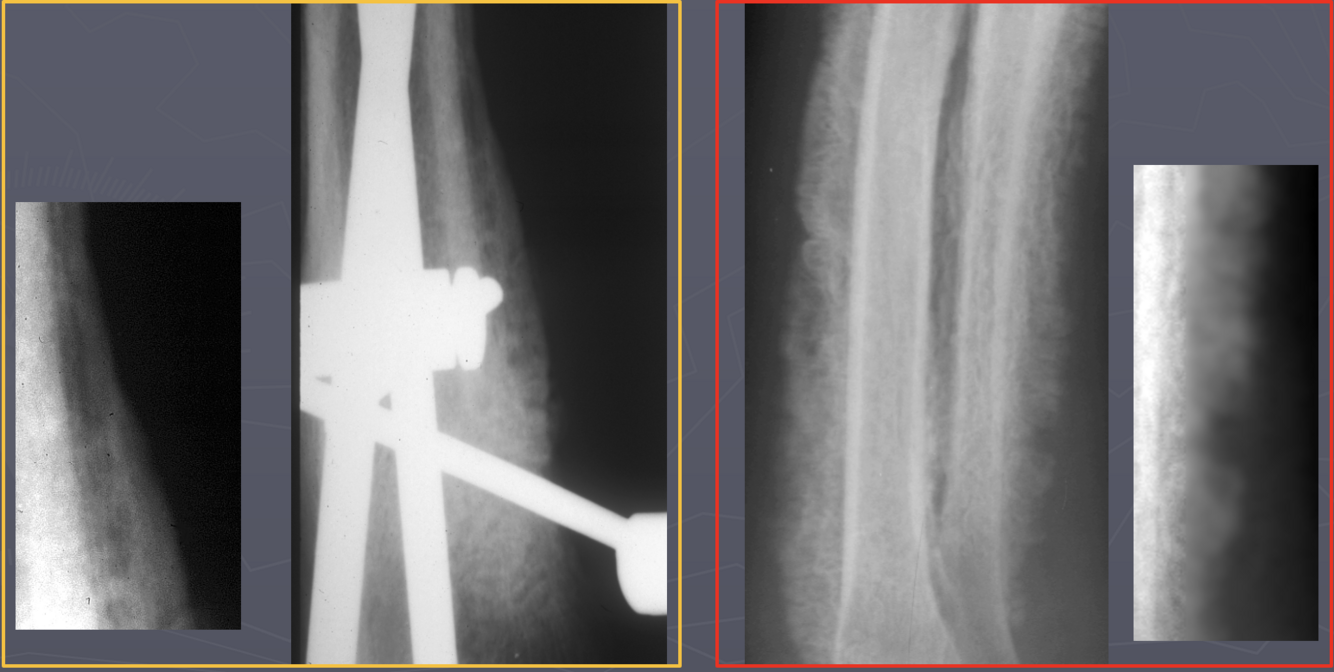

Which radiographs show an active vs. inactive pattern of periosteal reaction?

Left 2 radiographs: inactive; smooth, well defined margins

Right 2 radiographs: active; fuzzy, less sharp margins